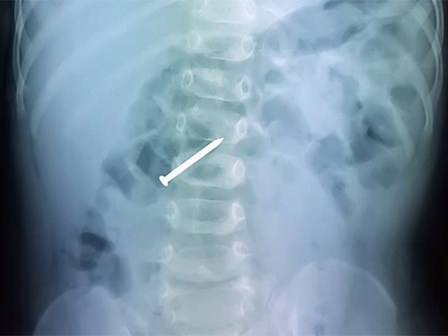

Chưa kịp ăn Tết, bé trai 2 tuổi đã suýt chết vì nuốt phải cây đinh rớt ra trong đồ chơi

Khi cha mẹ phát hiện đồ chơi bị rớt mất một chiếc đinh thì bé trai đã nuốt phải.